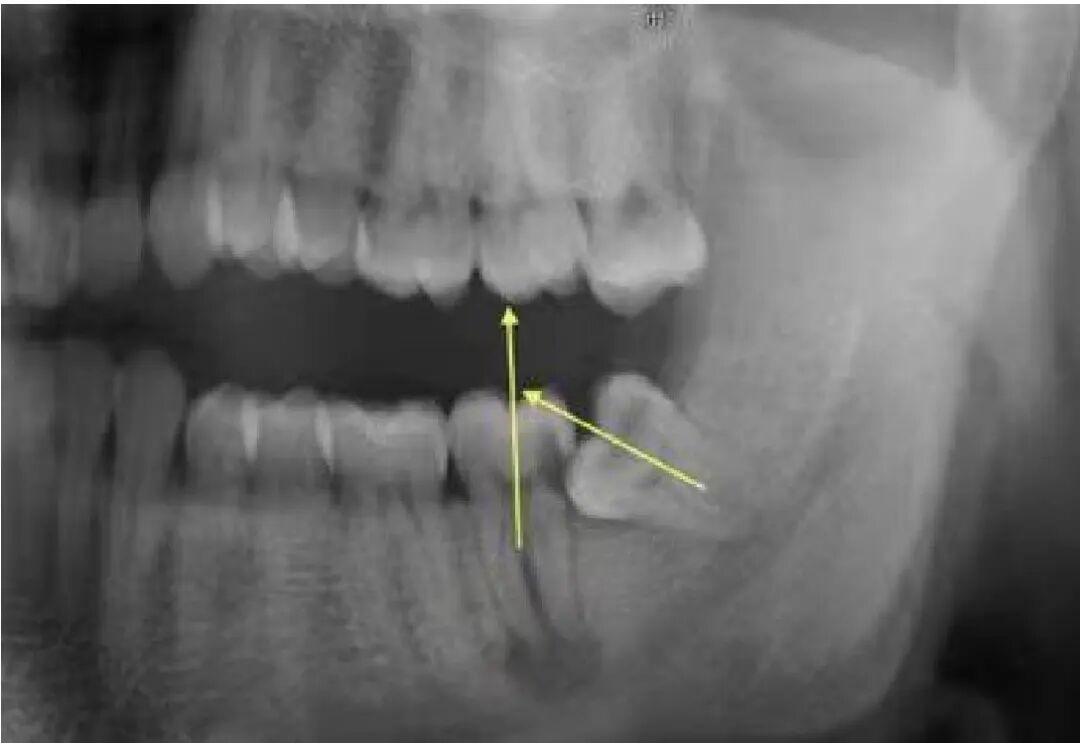

下颌阻生齿的常见分类

1)

下颌近中倾斜

高位阻生

在下颌第二磨牙中冠部外形高点以上部分为高位。

2)

中位阻生

阻生齿-04.jpg

冠部外形高点线与髓室底之间部位为中位。